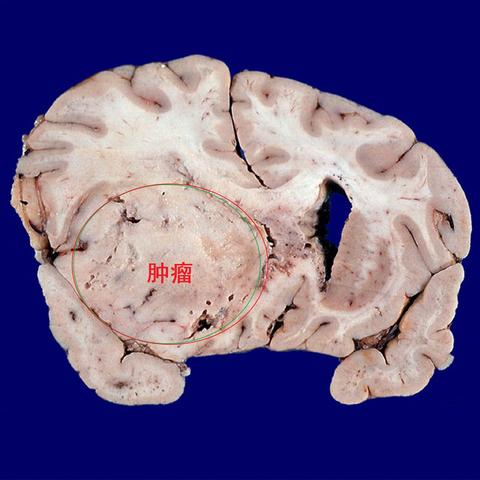

左额叶脑继发恶性肿瘤一例